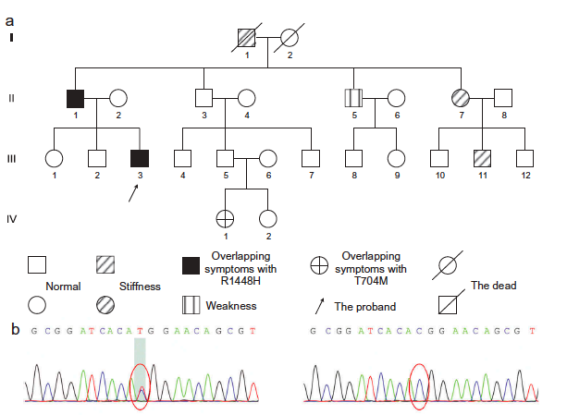

另一个家系中部分成员被诊断为SCN4A基因突变(R1448H)所致先天性副肌强直合并低钾型周期性麻痹2型�����。此外����,在此家系中一位具有重叠症状的患者为SCN4A基因T704M突变而非R1448H突变����。